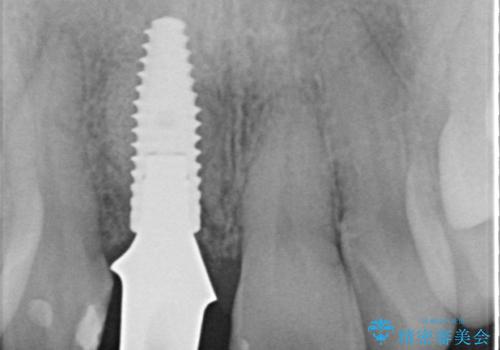

- 50万円(ストローマンインプラント・骨造成・ジルコニアカスタムアバットメント・ジルコニアクラウン)費用は治療当時の料金となります

前歯のインプラント治療は適切に行えば、ブリッジのように隣の歯を削らずに審美的で機能的な状態に仕上げることが可能です。

インプラント周囲に十分な骨や歯ぐきの厚みの整備を行うことで、審美的なインプラントの仕上がりを達成することができます。